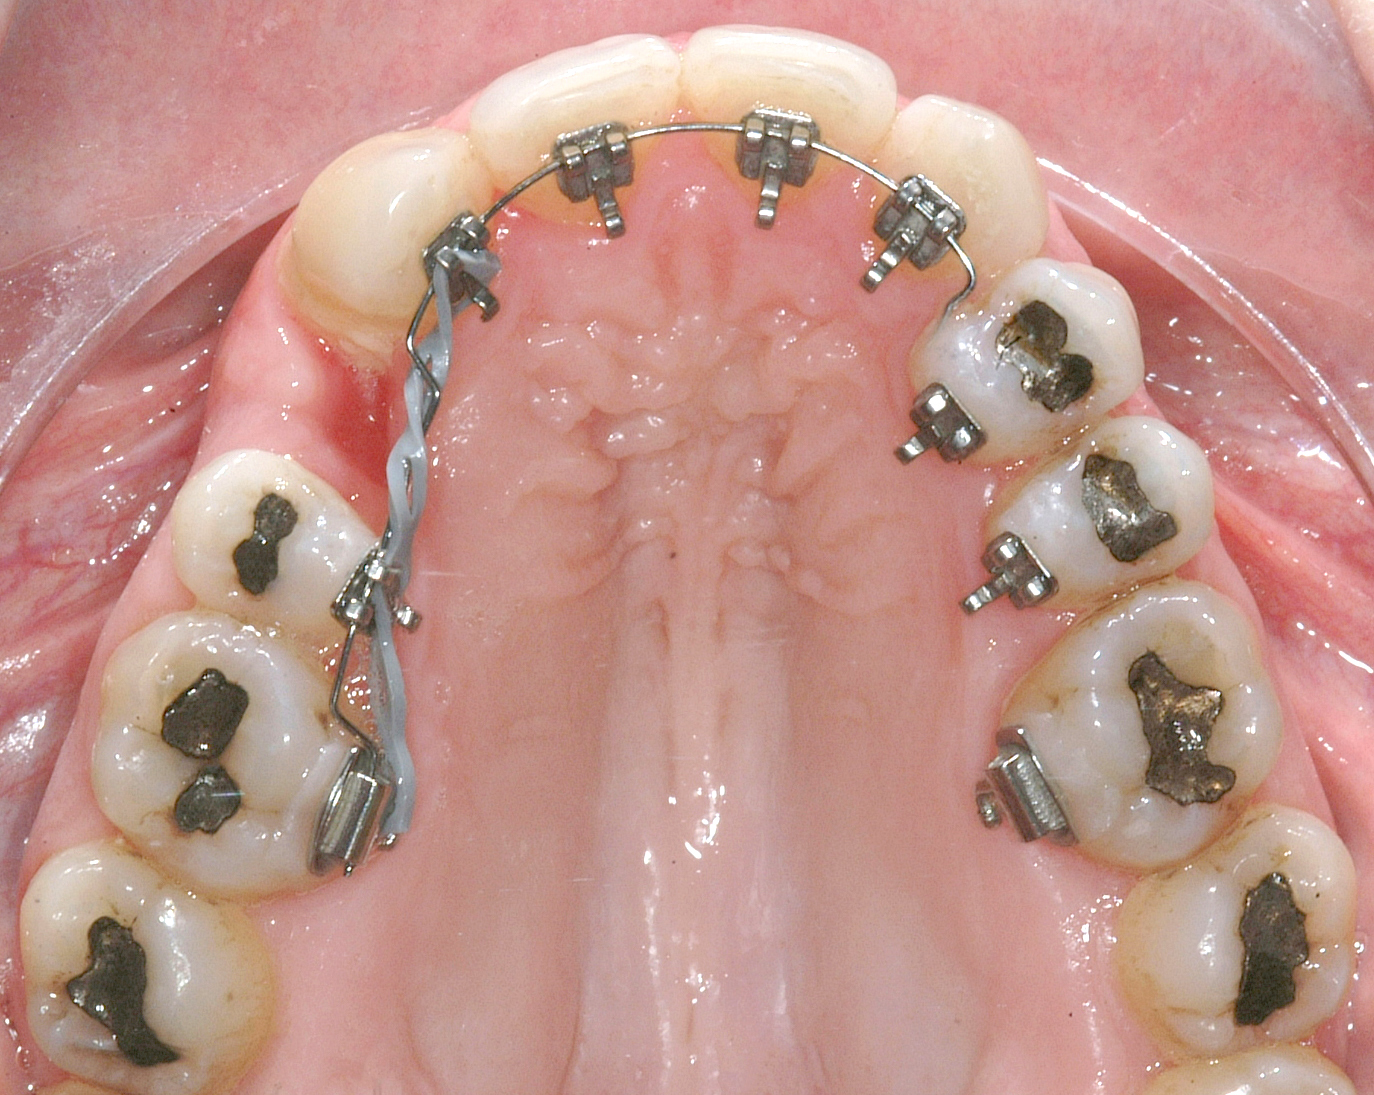

Il protocollo terapeutico ha previsto l’estrazione del primo premolare inferiore sinistro (3.4) e del primo superiore destro (1.4), l’applicazione di una apparecchiatura fissa linguale 2D e di una meccanica asimmetrica di ancoraggio e movimento ortodontico a entrambe le arcate (Figure 3a-b).

Il trattamento è iniziato con l’estrazione dei due premolari in unica seduta in anestesia locale e l’applicazione simultanea, dopo una settimana, della apparecchiatura linguale inferiore e superiore, non essendoci problemi di overbite e potenziali interferenze in occlusione tra l’apparecchiatura superiore e i frontali inferiori. All’arcata superiore è stata effettuata una iniziale chiusura dello spazio estrattivo con forze molto leggere in ancoraggio medio su arco .014” Nichel-Titanio e successivamente .016” Nichel-Titanio, bondato in prima fase per maggior stabilità direttamente sulla superficie mesiale di 2.4.